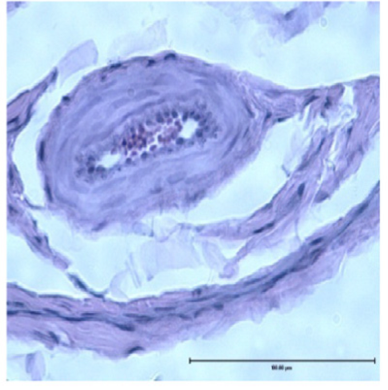

同时,科学家发现长颈鹿其他地方的血管壁也很厚,如下图

图源:文献1

科学家对长颈鹿心室壁和动脉血管壁厚度的发现,解释了为什么长颈鹿没得高血压的生理原因。人如果血压过高,这意味着心脏泵出来的压力实在太大了。这力量大了,“薄薄”的血管壁就遭不住了,所谓的脑溢血,就是因为血压太高,把脑血管壁给冲爆了。

而长颈鹿的心室壁和血管壁就不太一样了,它的血管壁贼厚,是人类的好几倍,这下即便是高血压,也不必担心把血管壁给冲破了。